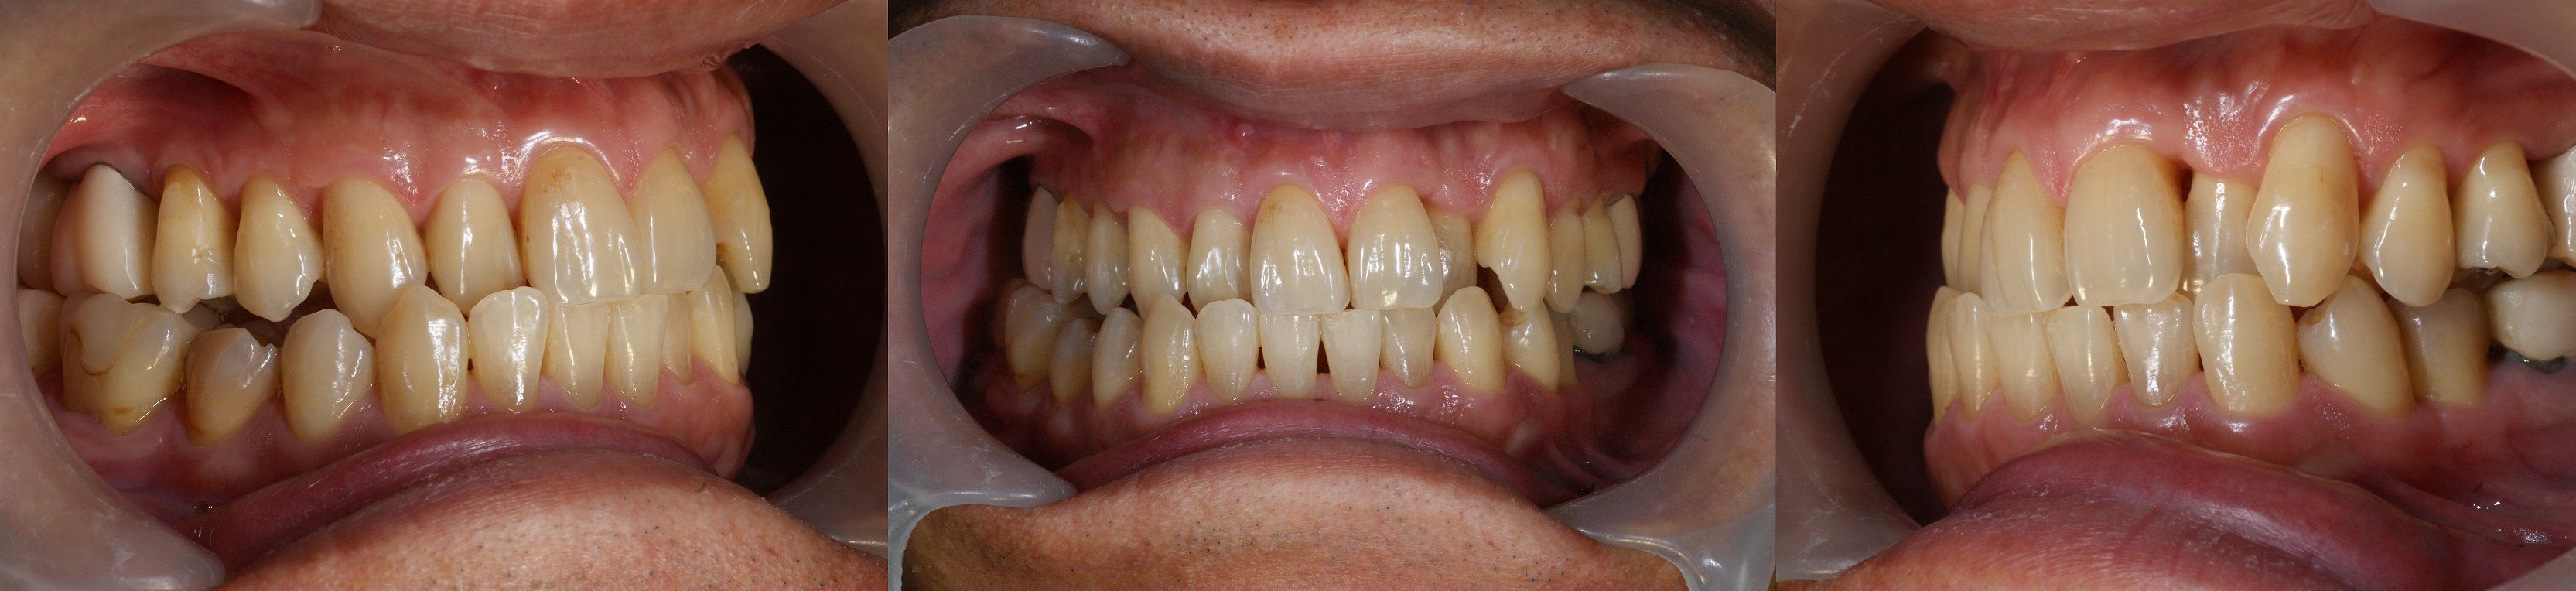

歯科矯正終了後、補綴せずに問題が起こらないならそれが理想的だが、今回の治療以前に長年にわたり(初診時54歳)、歯列不正(鋏状咬合)の状態で歯が使われてきたため、咬耗(歯の嚙む面の摩耗)が不均一で、そのままでは安定した咬合の確立が得られないことが診断用ワックス アップにより確認される。また歯周治療後に残された骨吸収を原因とする歯の動揺を収束するためにも補綴の必要性が問われる。(大)